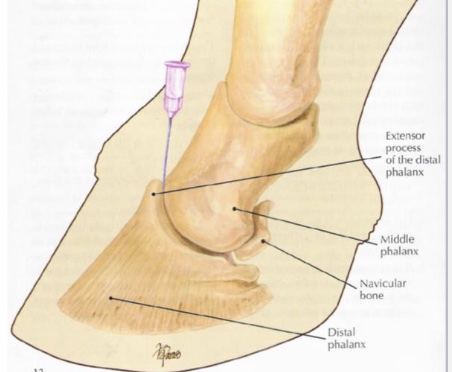

what is desensitized in distal interphalangeal joint

joint

navicular bursa

what is desensitized in a palmar/plantar nerve block

palmar/plantar 2/3 of foot

entire sole, navicular structures, distal interphalangeal joint, distal DDFT, distal sesamoidean ligaments